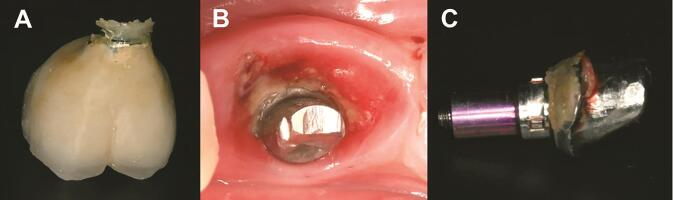

Retained cement results in peri-implantitis:

Retained cement results in peri-implantitis: ( A ) retained cement at the crown margin and excess cement in the peri-implant inflamed tissue, and ( B ) excess cement around the abutment. Reproduced from Ref. 23 with permission from John Wiley & Sons A/S.